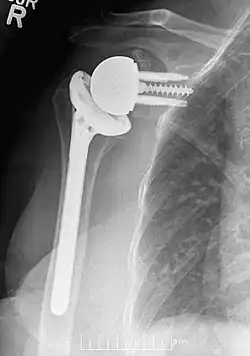

A artroplastia reversa do ombro é um tipo de artroplastia do ombro em que a relação normal de bola-e-soquete da articulação glenoumeral é invertida, criando uma articulação mais estável com um fulcro fixo.[1] Essa forma de artroplastia do ombro é utilizada em situações em que a cirurgia convencional de artroplastia do ombro levaria a resultados ruins e altas taxas de falha.[2]

Os implantes modernos de ombro reverso consistem em várias partes. No osso da escápula, há uma placa de base metálica que se desenvolve no osso da glenoide nativa, parafusos e/ou pinos que a mantêm no lugar e um componente metálico redondo de "glenosfera" que é acoplado à placa de base por meio de vários mecanismos diferentes. No osso do úmero, normalmente há um revestimento de polietileno côncavo que se articula com a glenosfera convexa e é fixado a uma haste umeral que cresce no úmero nativo ou é cimentada no lugar. Dentro dessa estrutura básica, há diversas variações diferentes de implantes e, até o momento, não há consenso sobre qual projeto é superior, embora vários estudos tenham demonstrado alguns benefícios de determinadas combinações.[9][10][11] Um desses sistemas modernos de implante de ombro reverso é o AltiVate Reverse. Mais informações sobre esse sistema podem ser encontradas no site da DJO.